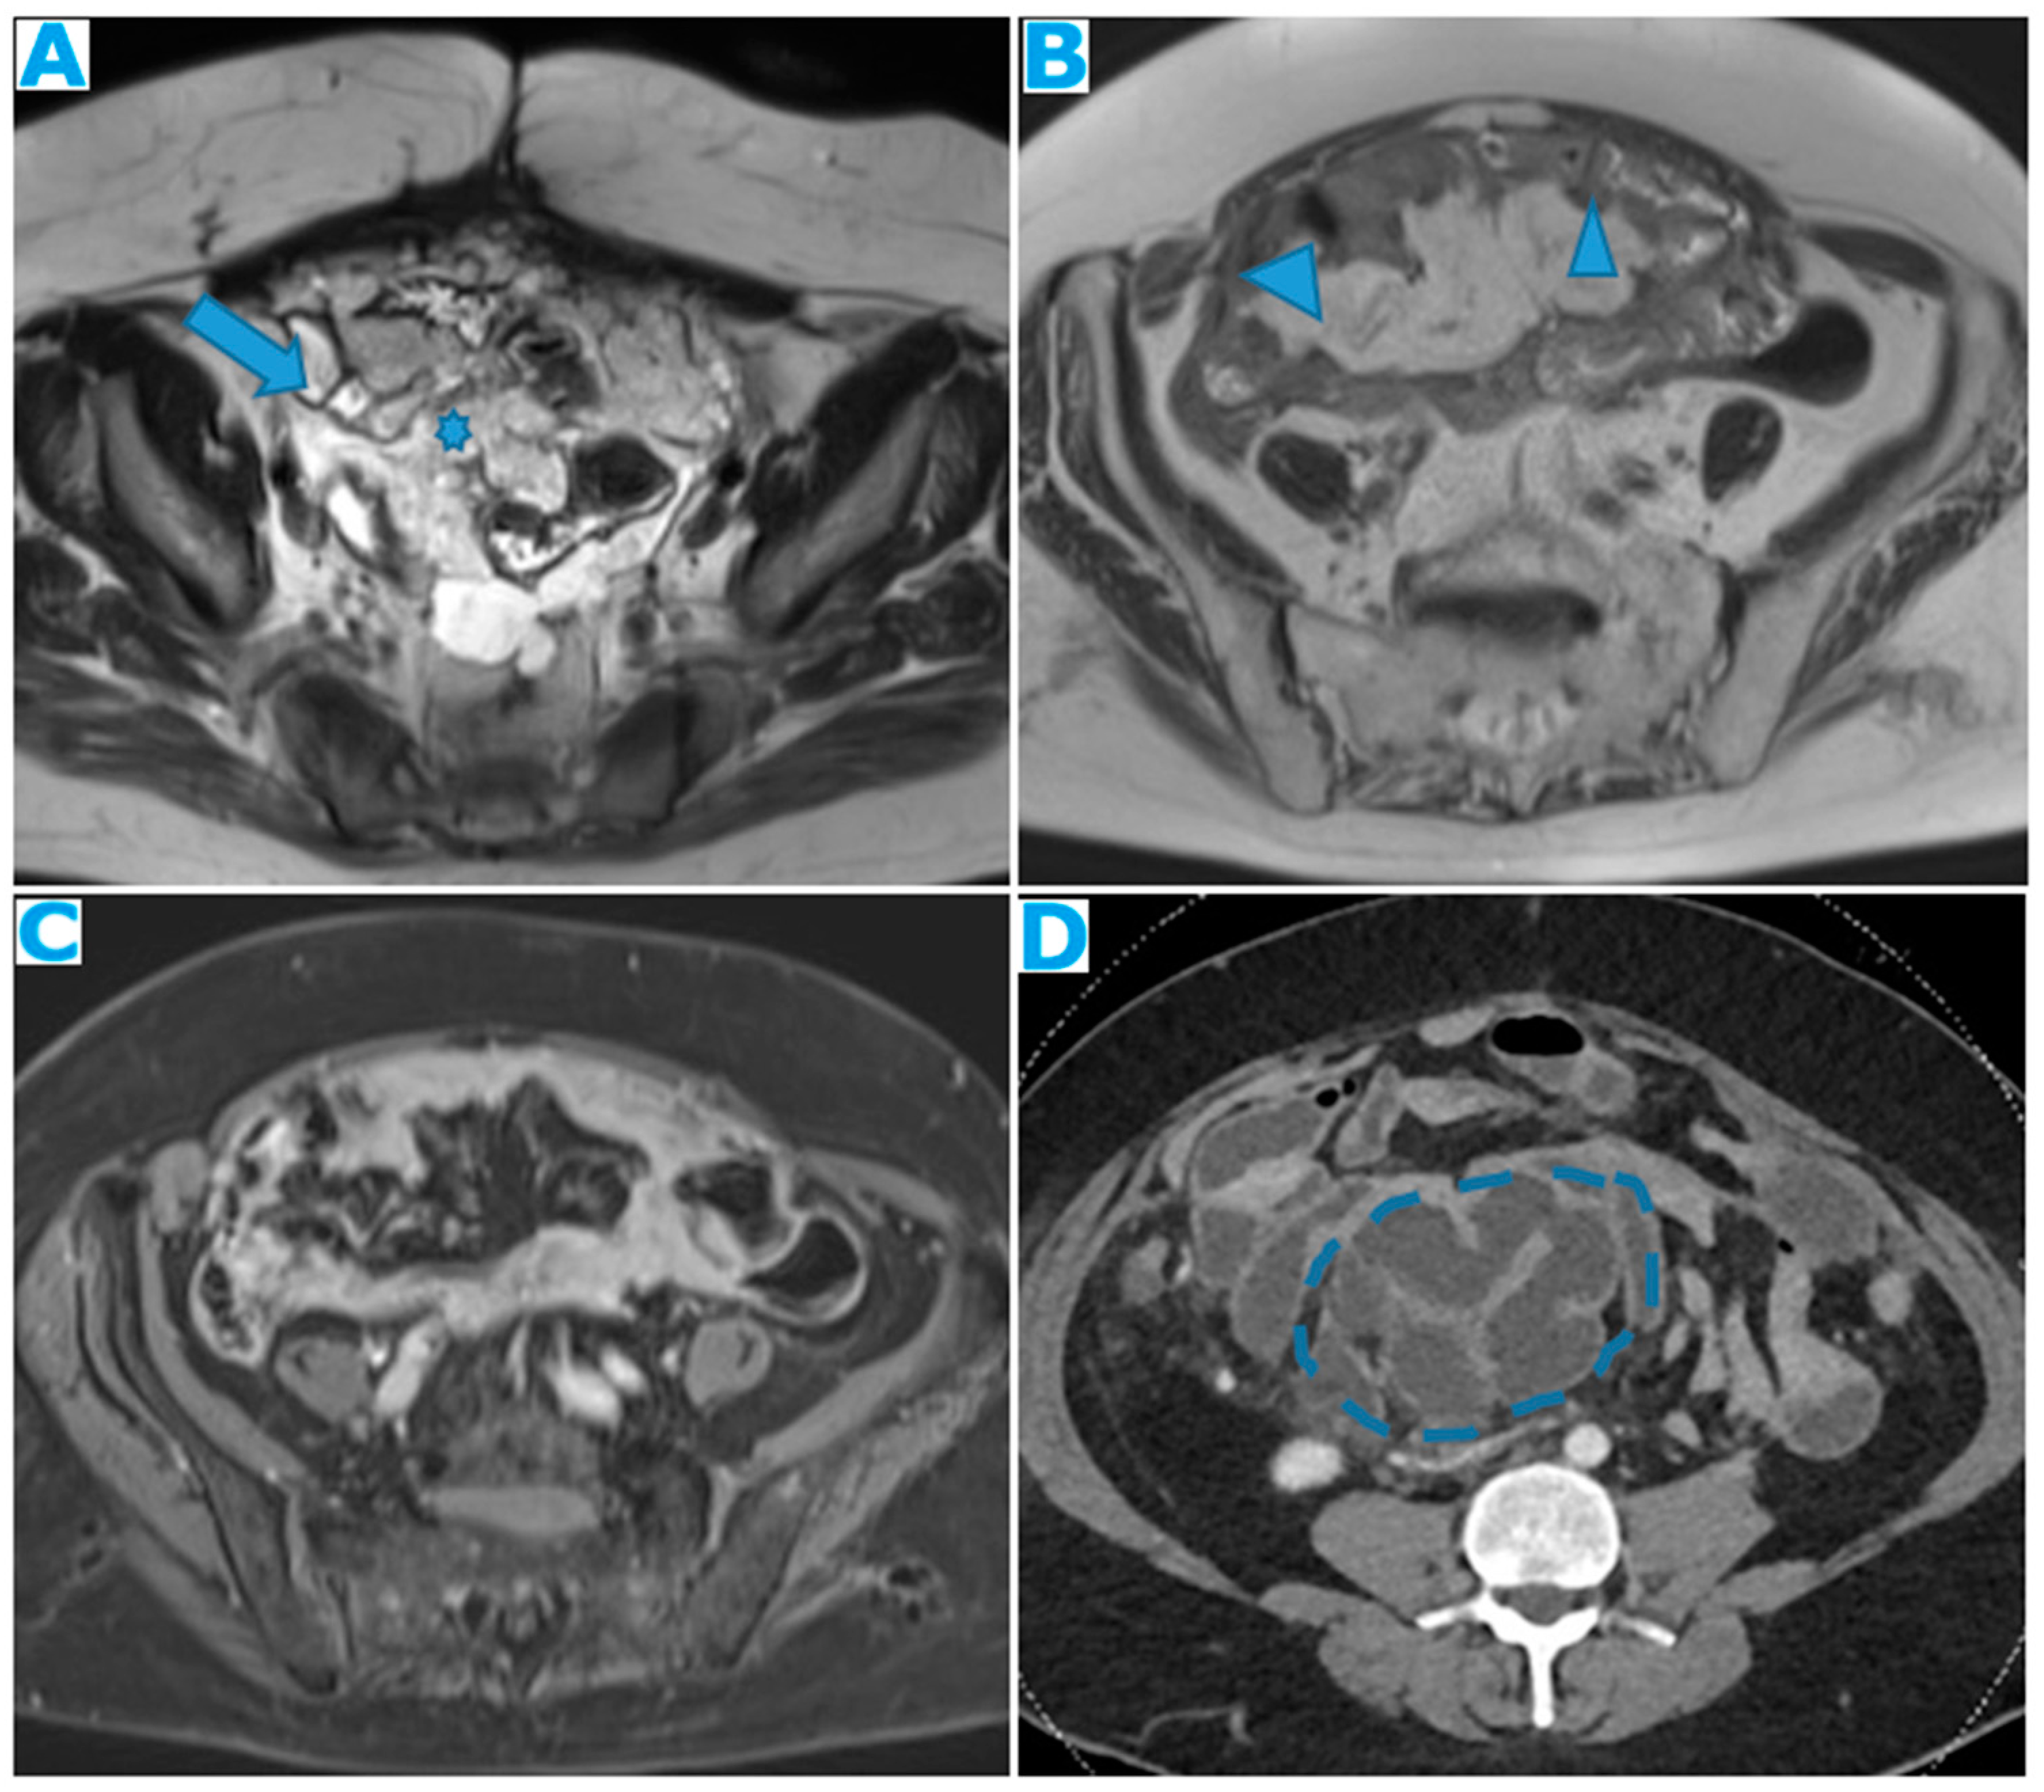

Figure 36.

Axial CE-CT (A). PC from sigmoid adenocarcinoma: Bilateral ovarian metastasis as complex cystic masses with solid poles. Axial CE-CT (B, D). PC from colon adenocarcinoma: Bilateral ovarian metastasis as solid masses. Axial T2WI (C). PC from mucinous tumour of the appendix: Left ovarian metastases (*) presenting as a predominantly hyperintense mass due to the mucin content.

Another common site of PC in the pelvis is the ovaries. As seen previously, they are extraperitoneal organs but considered intraperitoneal as they communicate with the peritoneal cavity. This is the reason why ovaries are included amongst the locations of PC.

Compared to primary ovarian tumours, ovarian metastases seem to be smaller, more frequently bilateral, showing more uniform cysts and more moderate enhancement of the solid portions [

18]. Although a solid appearance may also be found or even characteristics resembling the primary tumour (

Figure 36).

The term Krukenberg tumour is sometimes misused in the setting of ovarian metastases from a gastrointestinal tumour, as its use should be limited to ovarian metastasis from a poorly differentiated adenocarcinoma with signet ring cell features [

19]. Krukenberg tumour should be considered in the differential diagnosis when solid bilateral ovarian masses containing intratumoral cystic component are detected, even in the absence of a primary malignancy [

20].